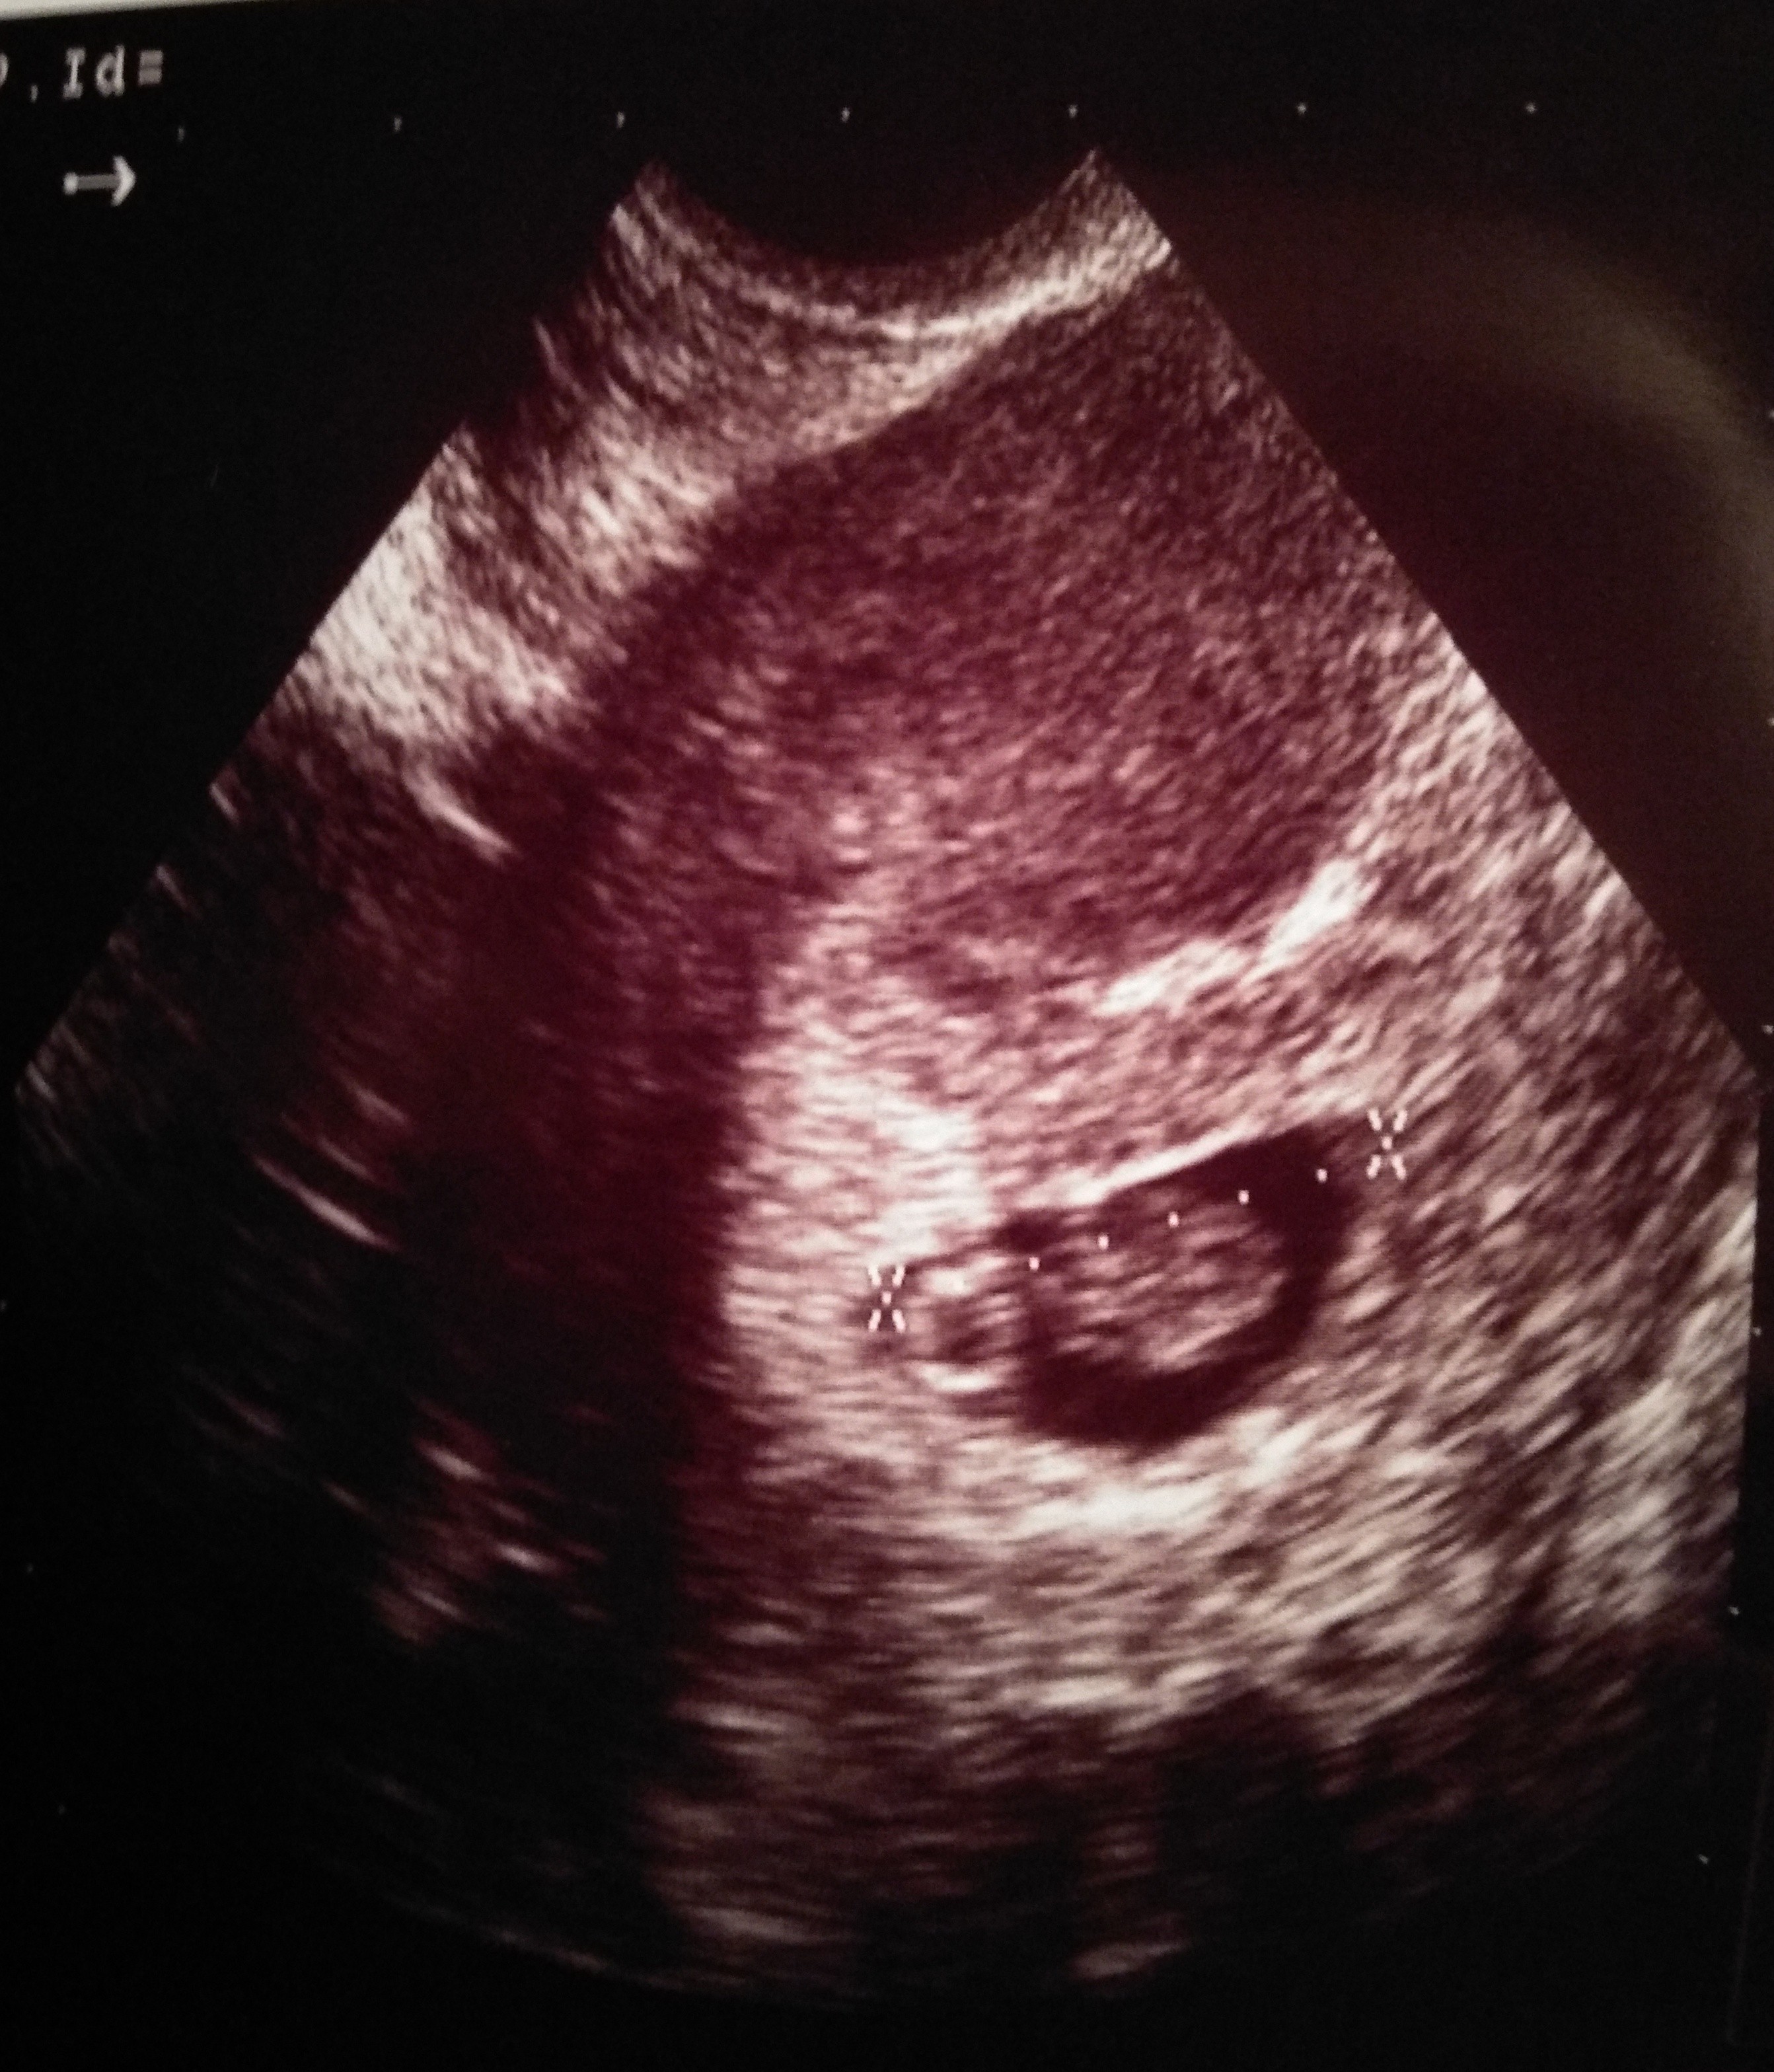

Mamy 1,01 cm :) O prawie tydzień do tyłu w stosunku do OM, ale mamy się dobrze i wg gin nadrobimy. Słuchaliśmy serduszka. Pięknie puka. Aaaa, no i torbiel na mniej niż 4 cm (10 dni temu miała 6 cm), więc jestem spokojniejsza.

P.S. Zmieniłam ginekologa - ta jest dużo bardziej komunikatywna, empatyczna i taka pro-ludzka.

Rano zjadłam ostatnią tab Duphastonu i chyba dobrze, że zapisałam się na wizytę, bo dostałam receptę na kolejne opakowanie. Była zdziwiona, że poprzednia gin kazała odstawić. Poza tym założyła kartę ciąży i kazała zapisać się na prenatalne. A Wy się już zapisałyście?

Kolejna wizyta 28.01.